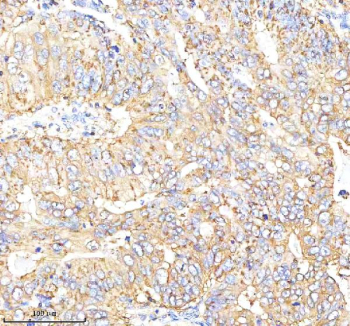

CGA Antibody Rabbit Polyclonal Stomach Cancer IHC. Immunohistochemical staining of Choriogonadotropin alpha/CGA using anti-CGA antibody rabbit polyclonal. Choriogonadotropin alpha/CGA was detected in a paraffin-embedded section of human stomach cancer tissue. Heat mediated antigen retrieval was performed in EDTA buffer (pH 8.0, epitope retrieval solution). The tissue section was blocked with 10% goat serum. The tissue section was then incubated with 2 ug/ml rabbit anti-CGA antibody overnight at 4oC. Peroxidase Conjugated Goat Anti-rabbit IgG was used as secondary antibody and incubated for 30 minutes at 37oC. The tissue section was developed using an HRP secondary and DAB substrate.